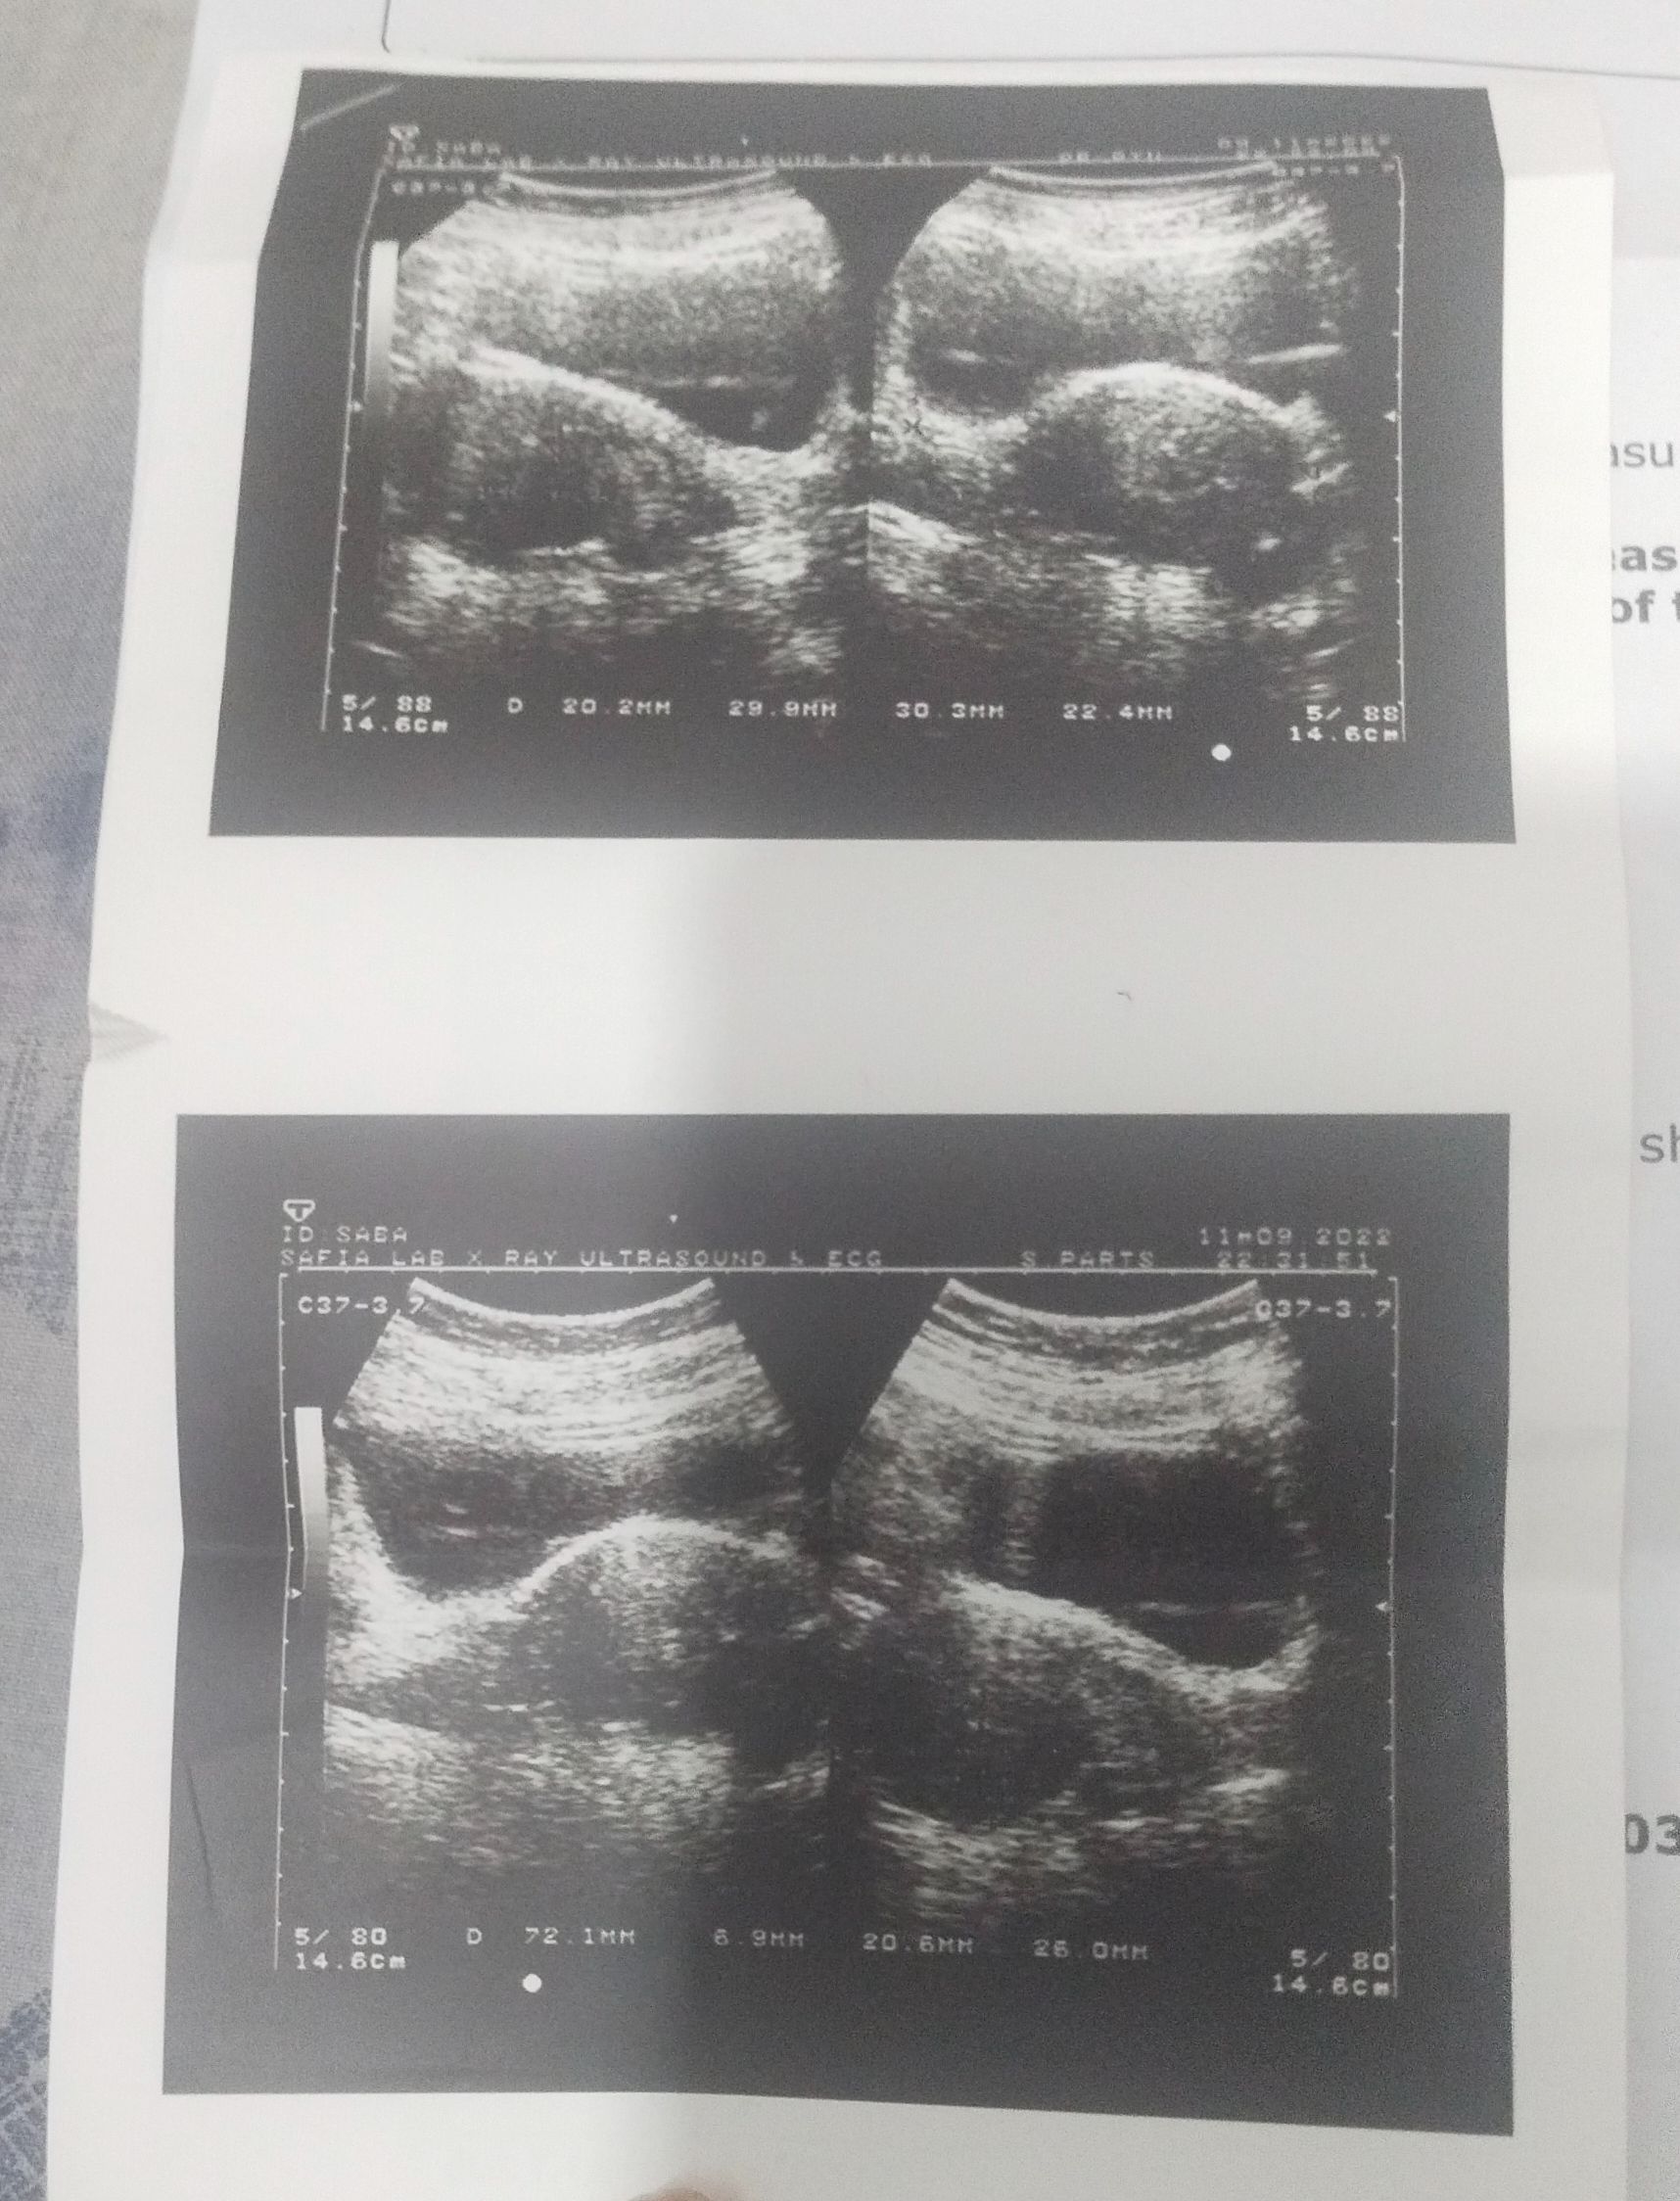

ap aik pelvic ultrasound keva Len then would decide further

G ye krwaya tha abhi...

Ye report

Ye rahi ultrasound report 22 November ki